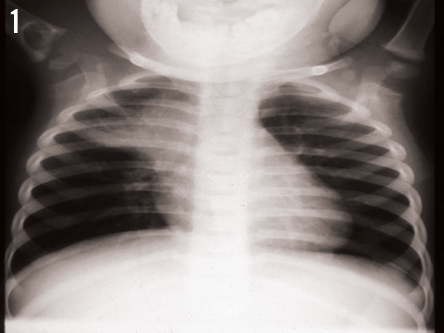

Laila Wilbur Powers, MD; Nazha Abughali, MD; Frits van der Kuyp, MD, MPH; David Effron, MD

The mother of an 18-month-old African American boy brought him to the emergency department with a chief concern of a swollen right shoulder.